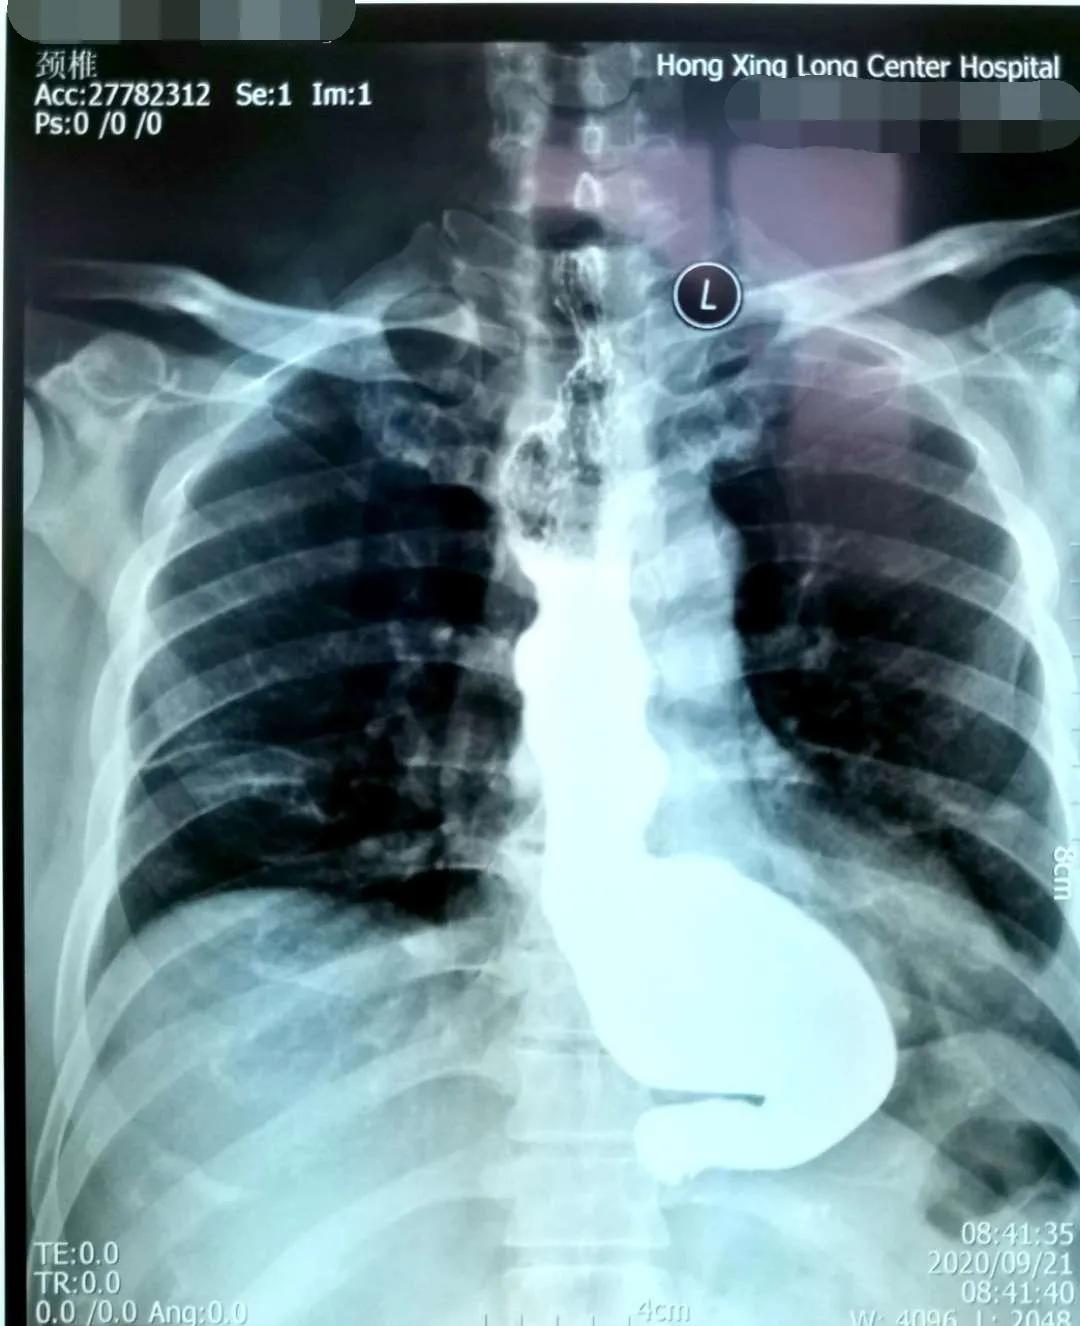

贲门失弛缓症又称贲门痉挛、巨食管,是由于食管神经肌肉功能障碍所致的疾病,临床表现为咽下困难,食物反流和下端胸骨不适,以及因食物反流误吸入气管所致咳嗽,肺部感染等症状。该病治疗不及时,有发生食道癌的风险。

简要病史:患者吕某,男,54岁,因吞咽困难10年余,不能进固体食物,并伴有胸痛,近半年仅能进食流食,来我院诊治。